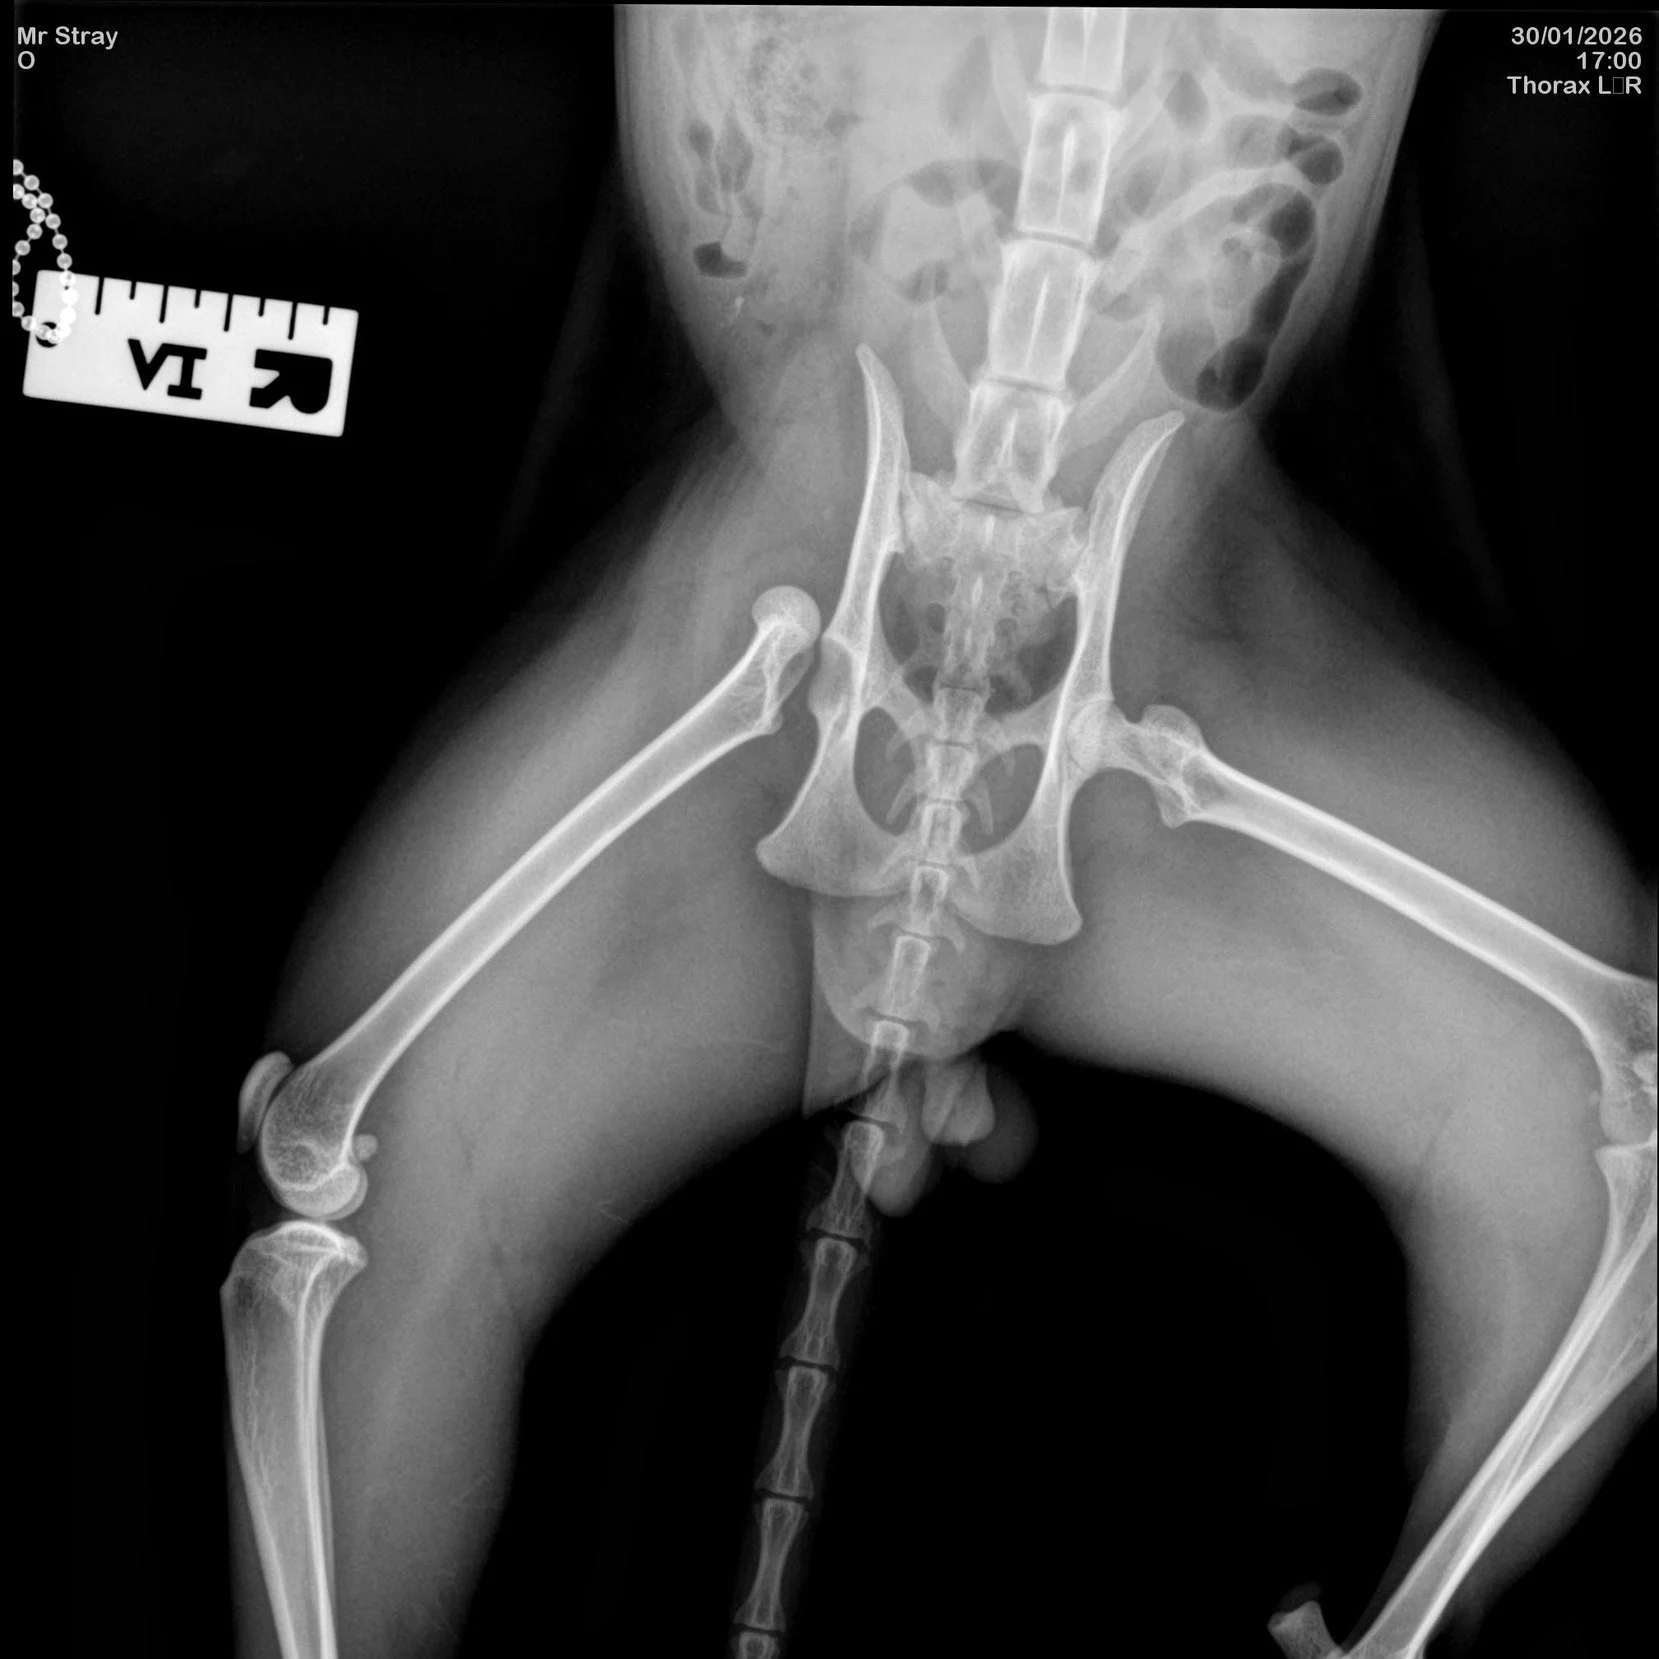

An x-ray image showing Elvis’s dislocated femur.

Elvis was found after being hit by a car, suffering an extremely painful dislocated femur. With no microchip and no owner identified, PAW Society stepped in to make a life-changing decision: amputate his leg or attempt complex orthopaedic repair.

Although amputation would have been the less costly option, the charity chose to pursue surgery to save his leg, giving Elvis the best possible chance of long-term mobility and quality of life. The surgery was successful, but his recovery requires ongoing monitoring, medication, and follow-up procedures.